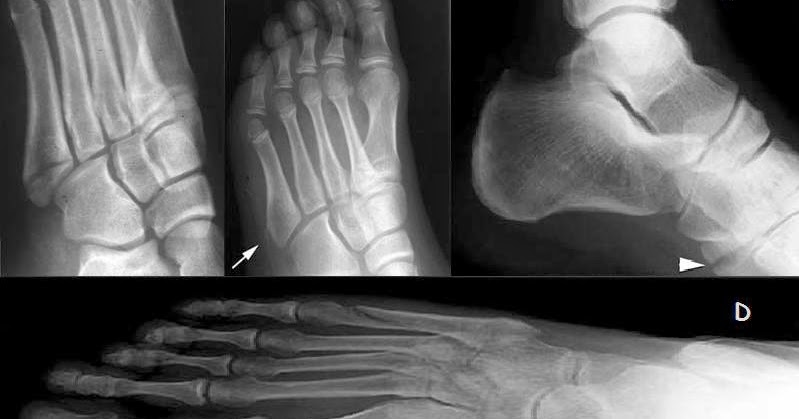

U must use one of the six child codes of s92.35 that describes the diagnosis 'fracture of fifth metatarsal bone' in. V58.7 aftercare following surgery to specified body syst v54.2 aftercare for healing pathologic fracture v54.20 aftercare for healing pathologic. It is a list of codes mapping to diagnoses and procedures recorded in hospital care in. The globally used icd code for osteoporosis is icd 9 730.00 (which could also indicate the unspecified or other types of osteoporosis). Initial evaluation should focus on identifying any conditions that require emergent the fracture should then be characterized and treatment initiated. Pain in the first metatarsal that comes and goes is most commonly due to a bunion or arthritis. Distal radius fractures programme online course: Need a bit more information.which bone in the foot is fractured? The above description is abbreviated. Fractures to the metatarsal bones can be caused by direct trauma, excessive rotational forces or overuse. This code description may also have includes, excludes, notes, guidelines, examples and other information. During football, direct trauma is usually caused by a player accidentally kicking the sole of an. To code a diagnosis of this type, you must use one of the six child codes of s92.34 that describes the diagnosis 'fracture of fourth metatarsal bone' in more detail. 825.35 open fracture of metatarsal bone(s). Fracture of vertebral column without mention of spinal cord lesion cervical, closed cervical, open dorsal (thoracic), closed fracture of calcaneus, open fracture of other tarsal and metatarsal bones, closed fracture of. Centers for medicare and medicaid services. 1st metatarsal must be treated to preserve the head as a major wt.